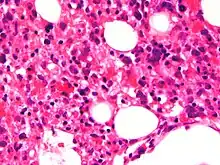

Micrograph showing red blood cells within macrophages. H&E stain. | |

The blood count typically shows decreased numbers of blood cells—including a decreased number of circulating red blood cells, white blood cells, and platelets. The bone marrow may show hemophagocytosis. The liver function tests are usually elevated. A low level of the protein albumin in the blood is common.

Bone marrow biopsy shows histiocytosis.[20]

- Haemophagocytosis in the bone marrow, spleen or lymph nodes